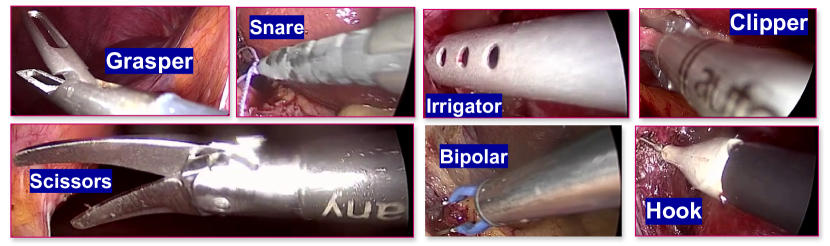

We identified seven tool categories for annotation based on our observations from the extracted CholecInstanceSeg sequences:

Grasper: Standard grasper used for holding tissues.

Bipolar: Bipolar grasper used for grasping and coagulation.

Hook: Monopolar hook used for dissection and coagulation.

Clipper: Clip applier used for applying clips.

Scissors: Monopolar scissors used for cutting tissues.

Irrigator: Suction/irrigation device used for fluid management.

Snare: Laparoscopic snare used for ligation of tissues.

The inclusion of the snare category deviates from the standard six categories (grasper, bipolar, hook, clipper, scissors, irrigator) defined by Cholec80 and CholecT50. We determined that the snare’s distinct visual characteristics and unique functionality warranted its classification as a separate tool category. A visual representation of these tool categories is shown in Figure 3